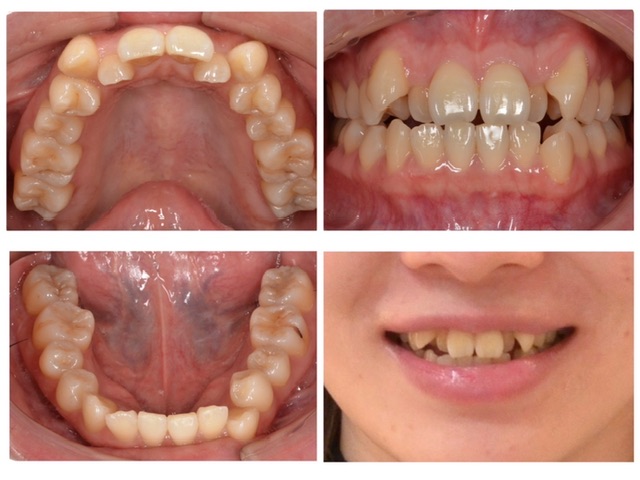

歯並びが気になる2024.10.11

主訴・術前 歯並びが気になる 術後の患者様の感想 気になっていた歯並びが綺麗になったのでとても嬉しく思います。歯の形や大きさなど質問をするたびに教えてくれたので矯正治療を行いながら知識はついたかなと思います。 ワイヤーが外れたり装置が取れて…